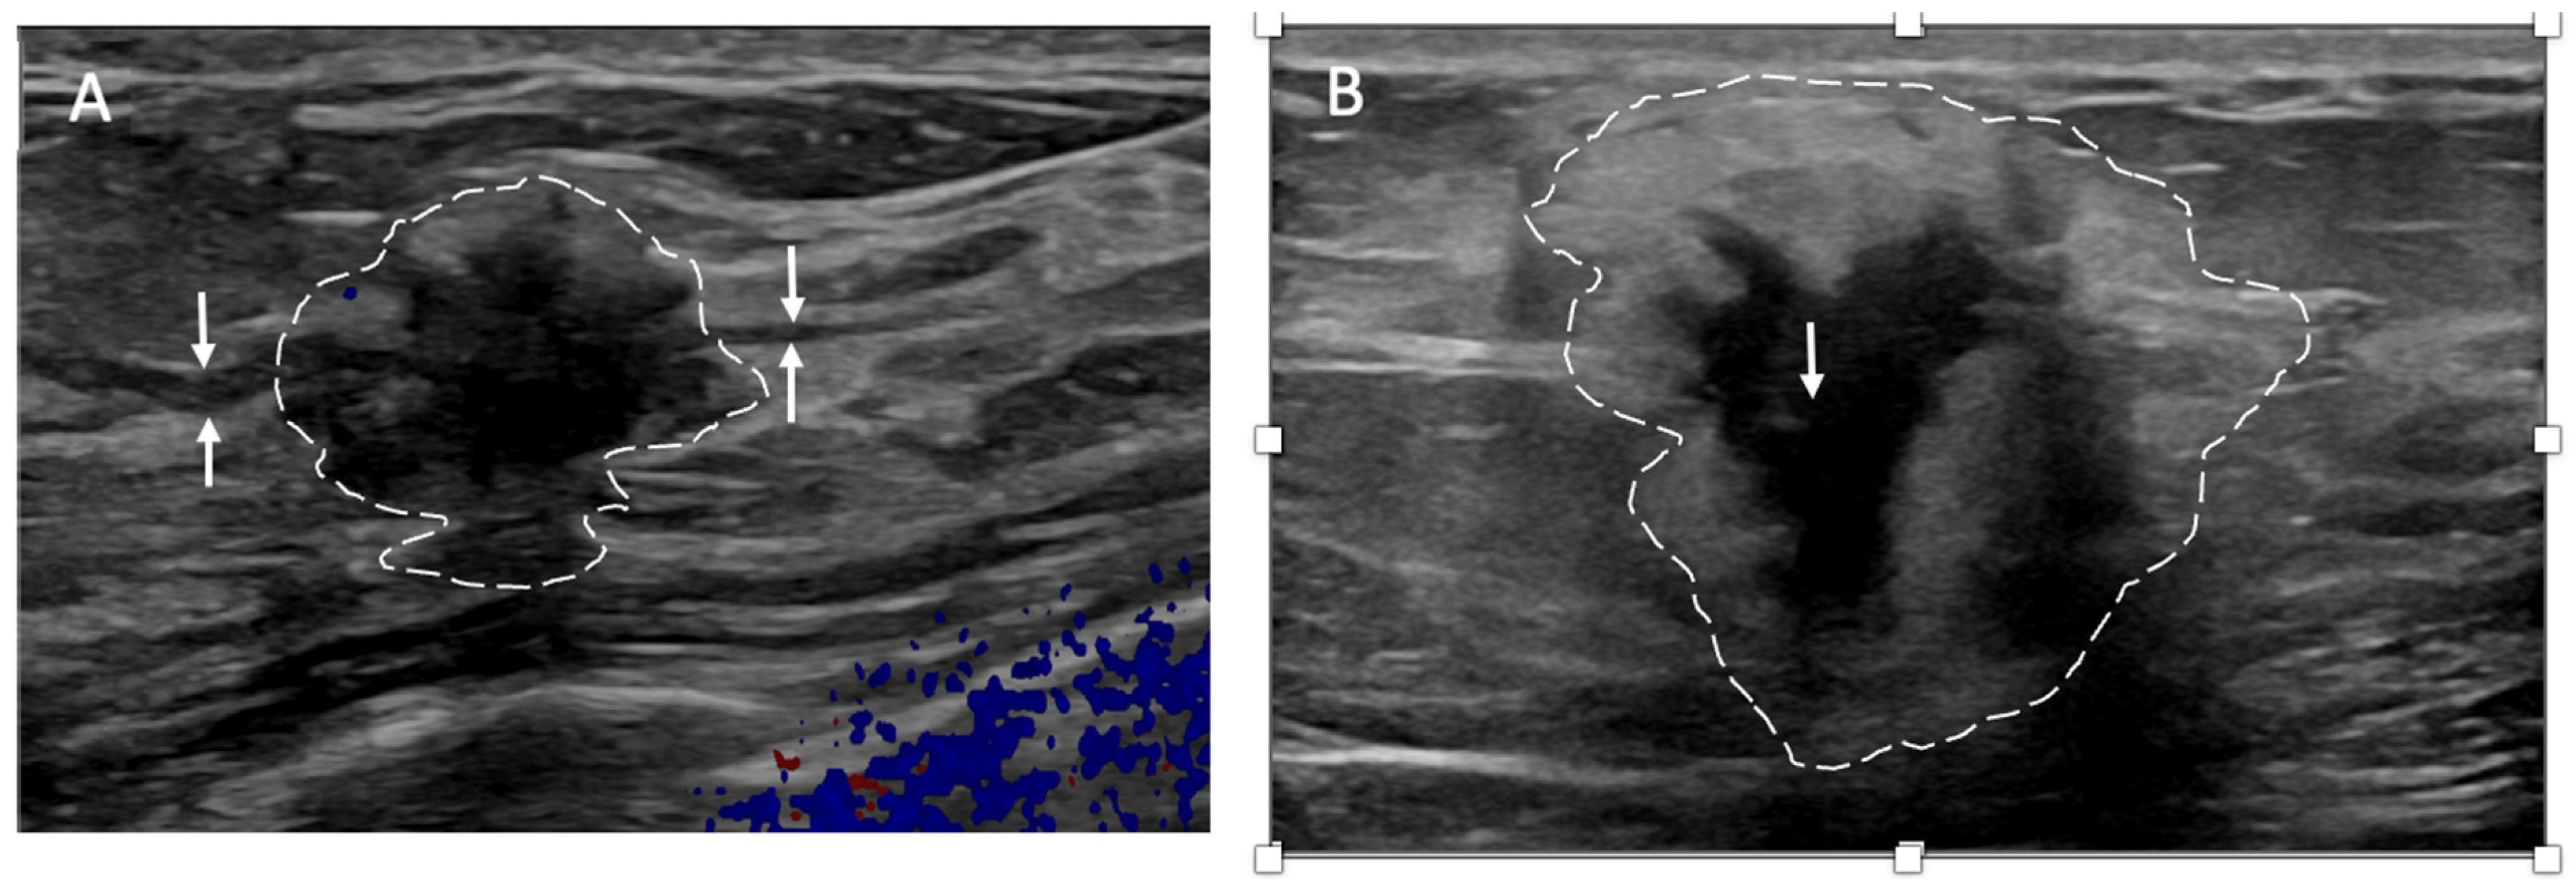

Ultrasound of the axilla. Axillary ultrasound permits the detection of abnormal appearing lymph nodes that might not be detected on physical examination, mammography, or breast MRI. Axillary ultrasound is the most sensitive imaging study for the detection of subtle changes in the shape or thickness of a lymph node cortex that might indicate the presence of lymph node metastasis (Figure 3). Detection of suspicious lymph nodes determines clinical cancer stage and requires a specific plan to manage the possibility of lymph node metastasis.

Figure 3.

Hash marks outline abnormal appearing axillary lymph node measuring 1.5 cm in maximal diameter. Paired “+” marks indicate the span of a 0.4 cm area of focal cortical thickening that is suspicious for a metastatic deposit within the lymph node.

Despite the surgical advancements to minimize the burden of lymph node surgery, some patients with positive lymph nodes continue to refuse lymph node surgery. In the context of patient centered care, some patients with limited nodal disease may be considered for lymph node cryoablation in lieu of surgery (Figure 17). Lymph node cryoablation entails several important considerations. Unlike cancers in the breast, the encapsulated nature of lymph nodes obviates the need for cryoablation of a wide surgical margin. Thus, cryoablation freeze times may be cut short when the dimensions of the iceball extend 5 mm beyond the lateral edges of the lymph node. However, lymph node cryoablation is not without hazard. Although lymph node cryoablation is a minimally invasive procedure, the elongated shape of the oval iceball typically causes the cryoablation zone of necrosis to extend 10–15 mm beyond the near and far edges of the lymph node, which can inadvertently cause cryoablation or injury to adjacent nodes, vessels, or nerves. Furthermore, since cryoablation does not permit axillary reverse mapping, lymph node cryoablation is comparatively less targeted and potentially more morbid than selectively removal of grossly abnormal axillary lymph nodes.

Figure 17.

(A) shows a grossly abnormal 1.1 cm axillary lymph node prior to insertion of cryoprobe. (B) shows an abnormal lymph node (outlined with hash marks),the cryoprobe traversing the lymph node (white line indicated by arrows), and projection of the cryoprobe tip beyond the distal end of the lymph node (linear hash marks) prior to beginning first freeze cycle.